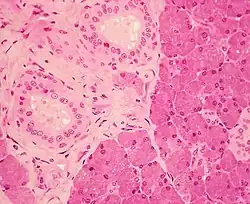

Histology

The parotid gland

The gland has a capsule of its own of dense connective tissue but is also provided with a false capsule by the investing layer of the deep cervical fascia. The fascia at the imaginary line between the angle of the mandible and the mastoid process splits into a superficial and a deep lamina to enclose the gland. The risorius is a small muscle embedded with this capsule substance.

The gland has short, striated ducts and long, intercalated ducts.[10] The intercalated ducts are also numerous and lined with cuboidal epithelial cells and have lumina larger than those of the acini. The striated ducts are also numerous and consist of simple columnar epithelium, having striations that represent the infolded basal cell membranes and mitochondria.[8]:273

Though the parotid gland is the largest, it provides only 25% of the total salivary volume. The serous cell predominates in the parotid, making the gland secrete a mainly serous secretory product.[10]